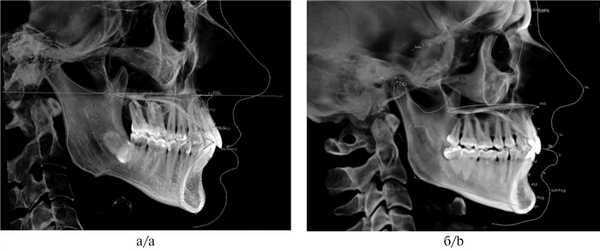

Рис. 1. Измерения в программе InVivo 5 Anatomage.

а — премаксиллярной зоны верхней челюсти (9,53 мм); б — длины мыщелковой ветви нижней челюсти (61,32 мм).

2. Измерение длины мыщелковых отростков ветвей нижней челюсти. Для того чтобы исключить скелетную природу асимметрии, обусловленную короткой ветвью нижней челюсти, необходимо провести измерение как мыщелковых отростков челюстей, так и мыщелков. Измерение мыщелковых отростков проводят параллельно касательной заднего края ветви между наиболее верхней точкой головки нижней челюсти Co (Condylion) и точкой Go (Gonion — нижняя точка угла нижней челюсти) (рис. 1, б) [1]. Для исключения наличия кондилярной деформации (гиперплазии или аплазии мыщелка) измеряют расстояние от точки Co (Condylion) до нижней точки нижнечелюстной вырезки (incisura mandibulae).